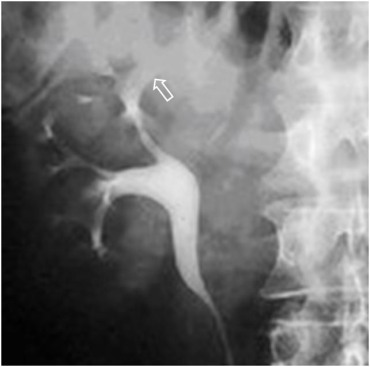

Radiografía simple y urografía intravenosa (UIV):

Es útil para localizar el calcio.

- De aspecto triangular en la necrosis papilar o focales.

- También pueden ser curvilíneas y lobares

- Amorfas y diseminadas en estadíos finales.

La realización de escopia con contraste es muy sensible, demostrando alteraciones en el 90% de los pacientes afectos.

- Cicatrices parenquimatosas.

- Estenosis infundibulares.

- Borrosidad (cáliz fantasma) o irregularidad de los cálices (apecto apolillado).

- Hidronefrosis.

- Dilataciones y estenosis del uréter (uréter arrosariado). El engrosamiento mural ureteral es mejor valorado en la TC.

- Afectación vesical con edema en inflamación mural con progresión a fibrosis y atrofia vesical. Las calcificaciones no son frecuentes en la vejiga.